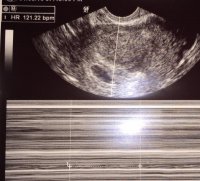

I've managed to upload my 8 week scan picture. I know how to do it now ! Hurray

I've managed to upload my 8 week scan picture. I know how to do it now ! Hurray